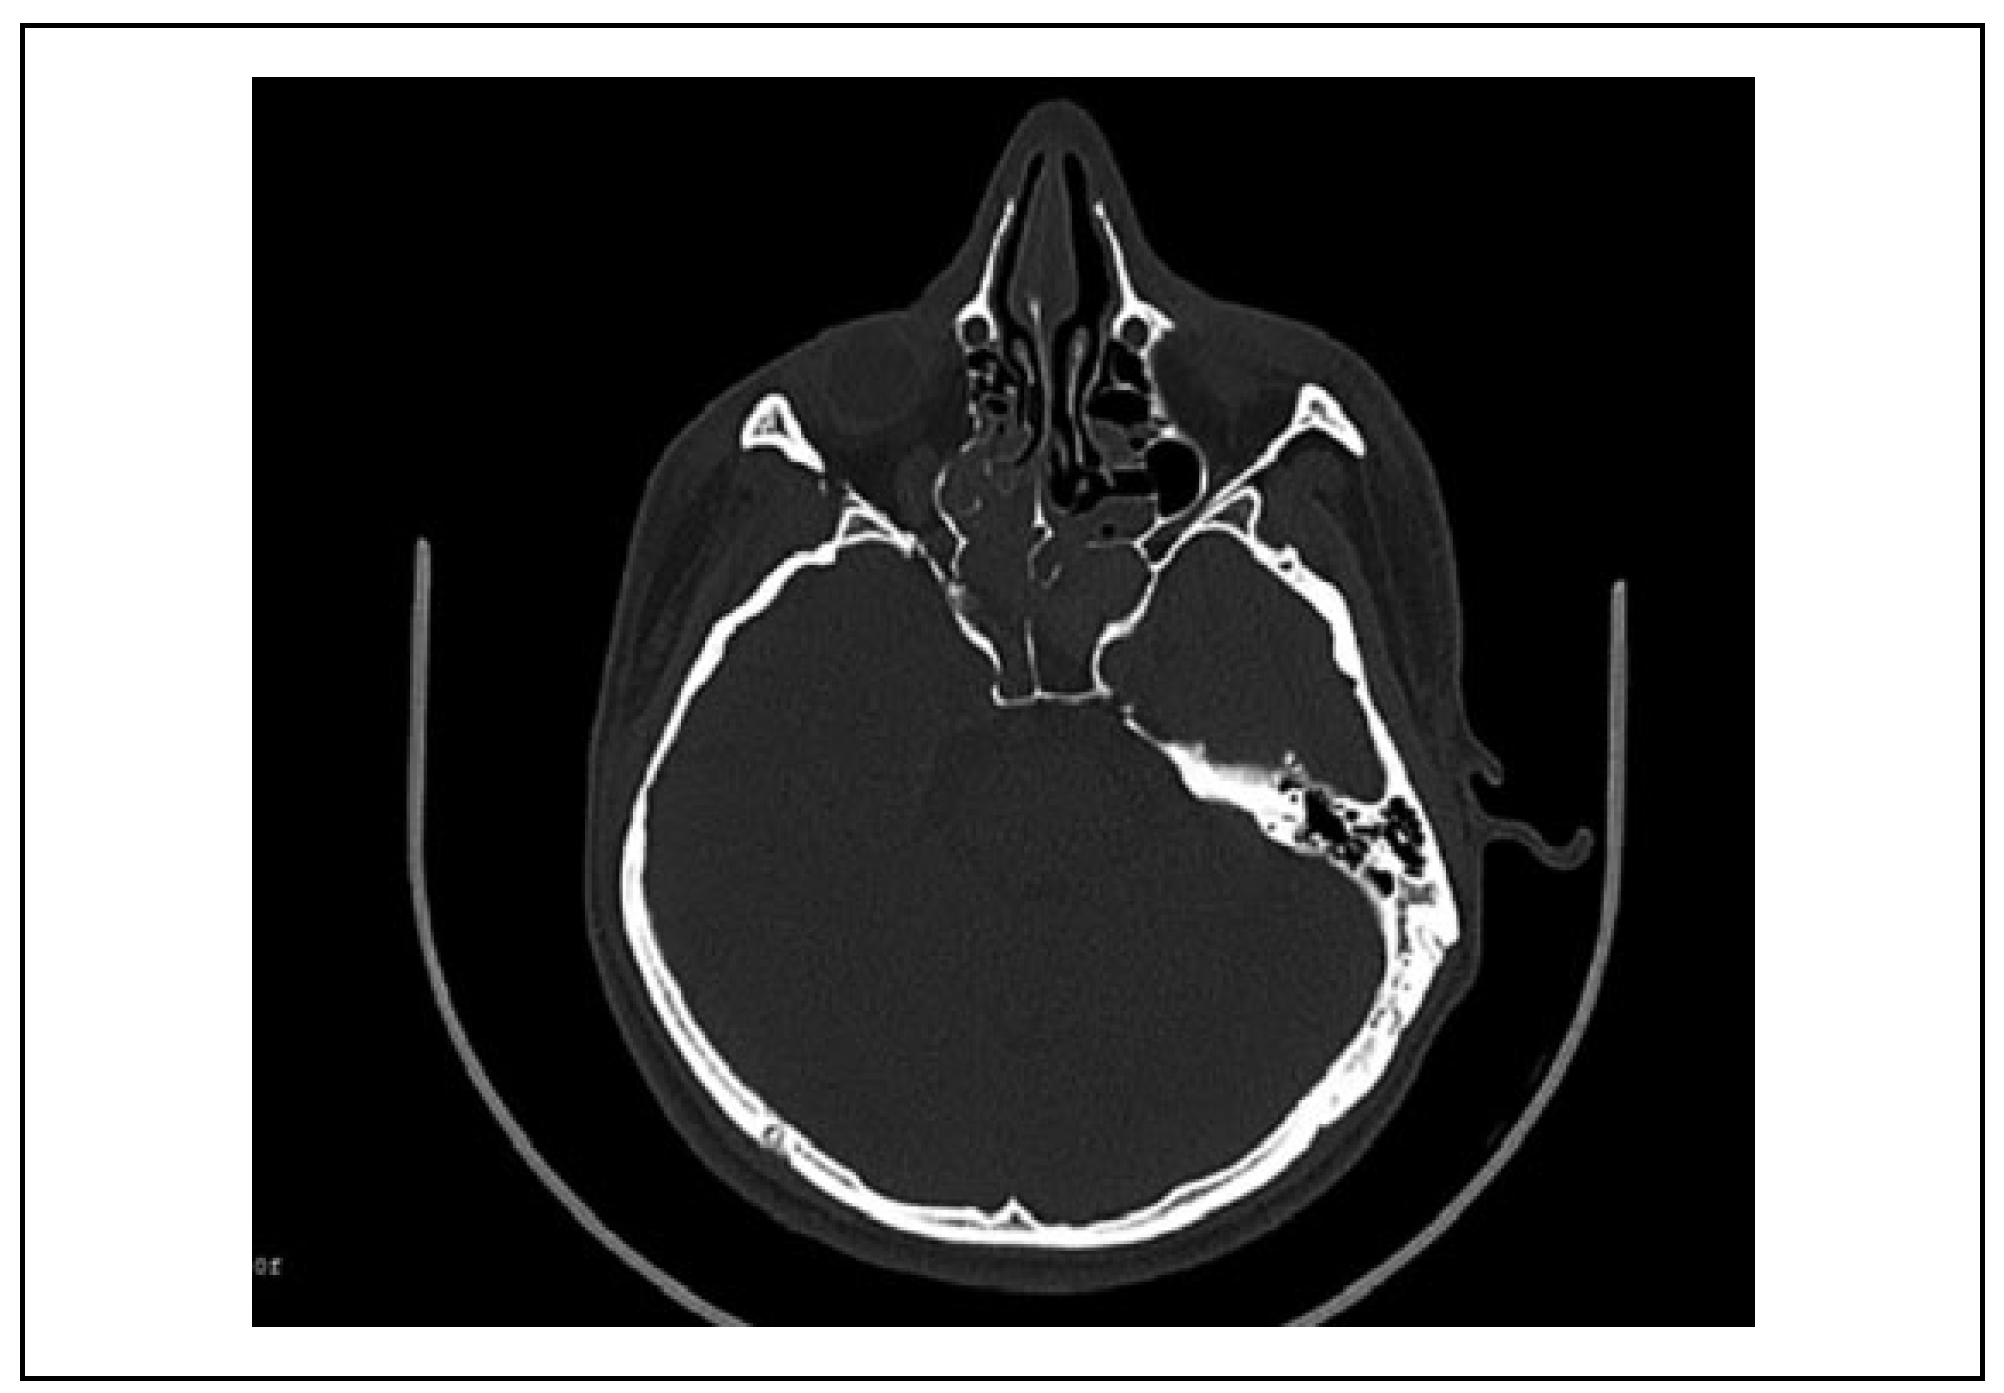

Case 1

Case 2

Case 3